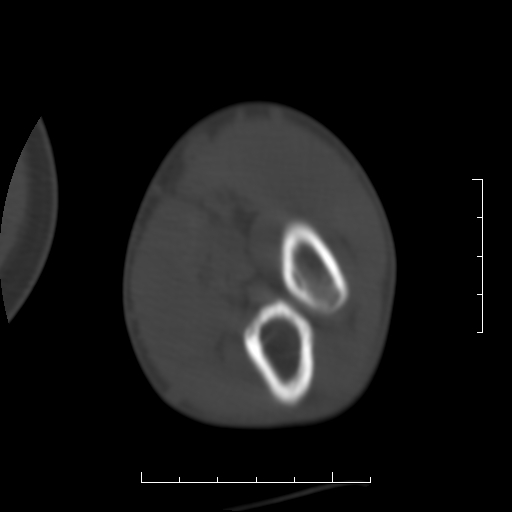

标题: CT8866:男27岁,正常吗?

患者男27岁,2007年3月查出患上肘关节滑膜结核,此后行手术滑膜剥除,今查ct

看一下上面的桡骨粗隆有问题吗?

桡骨粗隆有问题,术后改变

桡骨骨皮质破坏,结合病史考虑结核